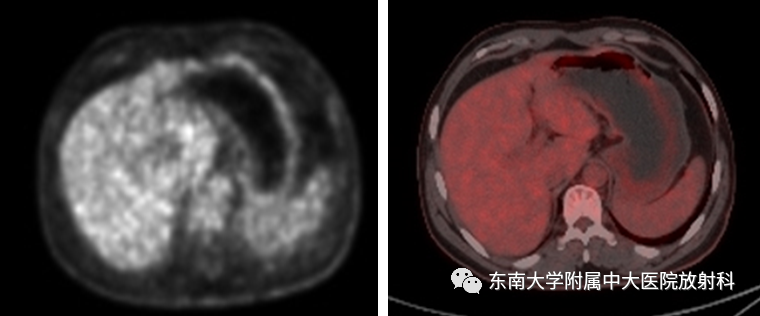

胃黏膜相关淋巴组织(MALT)淋巴瘤

病例

•男,49岁

•主诉:因“间断性腹痛、黑便4天”入院

•患者4年前无明显诱因下出现腹痛、为阵发性,夜间较重,无明显规律,解黑便数次。4年前于外院行“疣状胃炎APC术”,3年前于外院行“肠息肉内镜下粘膜切除术”;(2017-11-06)于外院行胃镜:胃体溃疡(淋巴瘤待排)